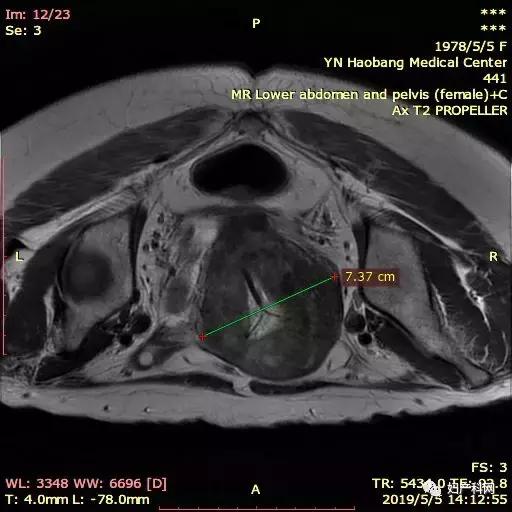

因为这个患者子宫比较大,同时还有比较重的贫血貌,所以就诊时查了一下血常规仅有60+g/L,这样的情况下直接治疗不仅难度大,术后恢复也相对比较慢。所以我们先给予了患者一只10.8mg的诺雷德,希望她能够这几个月不来月经,避免进一步的丢失,同时开始口服铁剂补血,从1月底患者就诊到4月安排治疗,3个月的时间血色素恢复到了102g/L,子宫腺肌症的范围也从1月的12×7×11cm缩小到了8×5×7.5cm,治疗当天我们使用经皮的微波治疗,功率50w治疗6min10s,60w治疗9min36s,进行超声造影消融满意,于宫腔内放置了曼月乐环1枚。